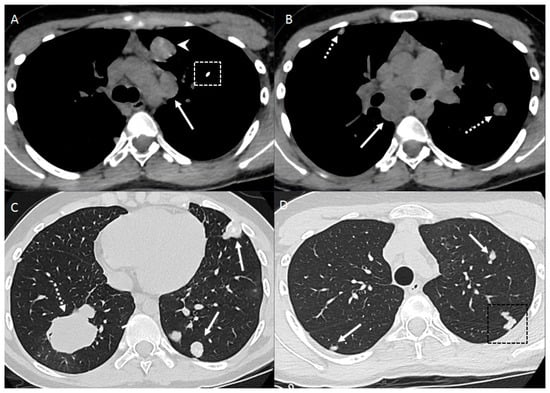

2.2. Vascular Metastasis

4. Mediastinum and Hilum

5. Cardiac and Major Thoracic Vessels

6. Chest Wall